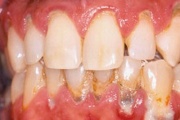

Krooniline parodontiit

Krooniline parodontiit on mikroobide poolt põhjustatud hammaste tugikudede põletik, mille tulemusena tekib progresseeruv alveolaarluu (nähtav röntgenograamil) ja periodontaalligamendi destruktsioon, igemetaskute moodustumine, igeme retsessioon või mõlemad kahjustused kombineeritult. Loe edasi »

- igemed veritsevad (19)

- igemed punetavad (21)

- ige on paistes (mädapunn)

- igemed on tursunud/vohavad (17)

- puudulik suuhügieen (5)

- igemepealne hambakivi (5)

- igemealune hambakivi (4)